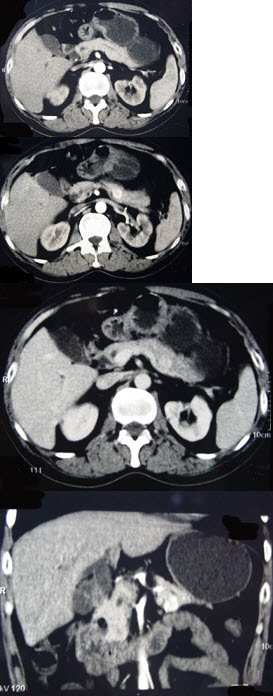

男性,57岁,1年前无明显诱因反复出现嗜睡及发作性神志不清,进食糖水或甜品后症状即缓解,腹部CT检查如下图,最佳的诊断是( )

A:胰腺癌

B:胰岛细胞瘤

C:胰腺转移瘤

D:胃泌素瘤

E:舒血管活性肽瘤